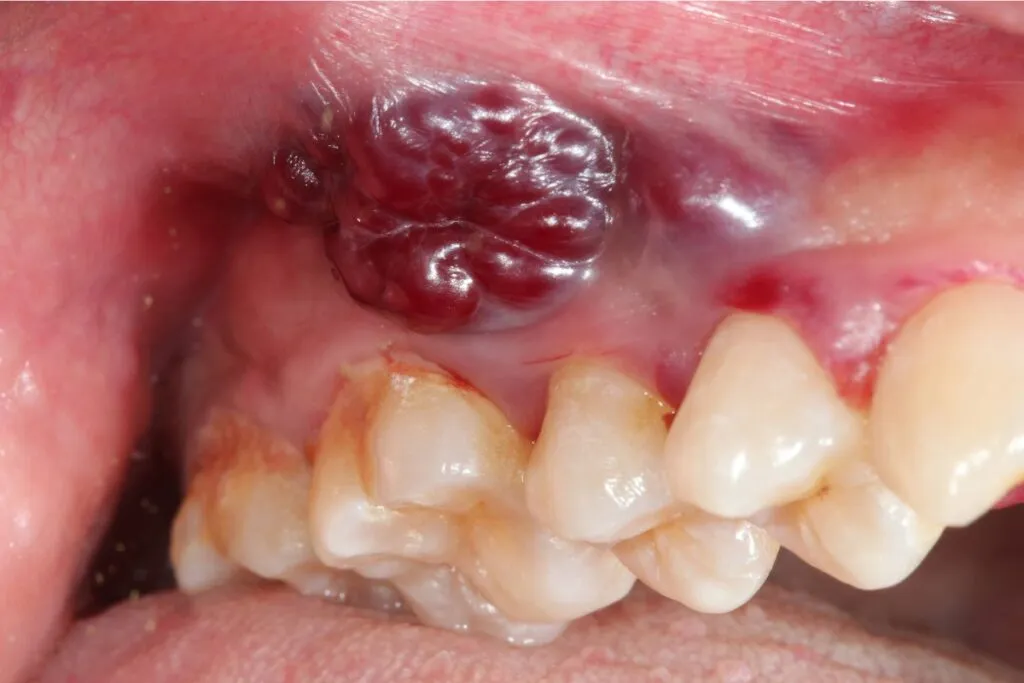

Widoczny guz w ustach lub na szyi: Jak odróżnić go od innych zmian?

Pojawienie się widocznego, twardego guza lub zgrubienia w jamie ustnej (np. na języku, dnie jamy ustnej) lub na szyi (powiększone węzły chłonne) to bardzo poważny sygnał. Guzy nowotworowe są zazwyczaj twarde, nieruchome i często niebolesne w początkowej fazie. Jeśli wyczuwasz taką zmianę, koniecznie i bezzwłocznie udaj się do lekarza. Nie próbuj diagnozować tego samodzielnie.